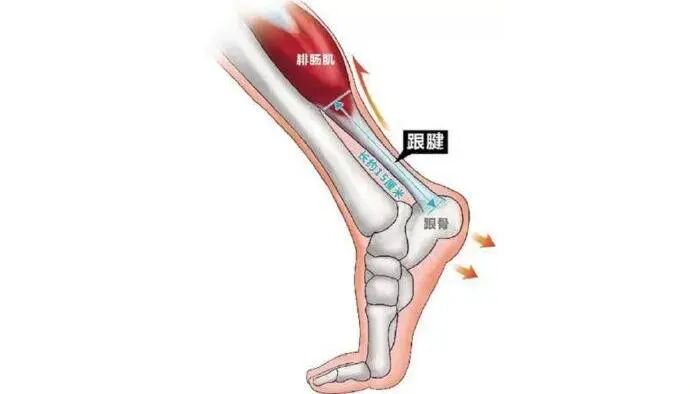

2、跟腱炎

跟腱是由连接小腿后方肌群与跟骨的带状肌腱纤维组成,当它在短时间内承受的压力过大时,可能会发生劳损、细微挫伤或撕裂,进而出现无菌性炎症,即跟腱炎。

示意图片来源于网络,侵删